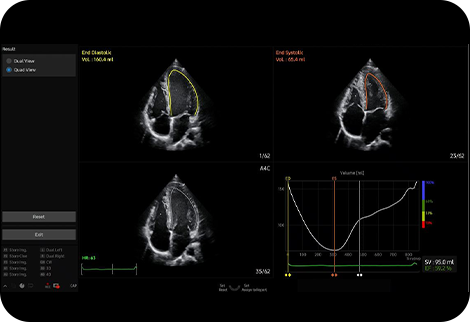

Měření ejekční frakce levé komory |

AutoEF je funkce, která pohodlně měří a kvantifikuje ejekční frakci. Výběrem tří bodů levé komory se vypočítá objem na konci systoly a na konci diastoly, což napomáhá rychlému a efektivnímu posouzení funkce srdce.